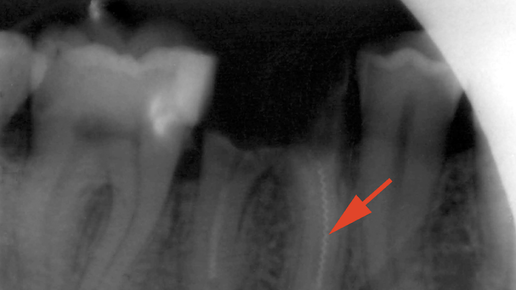

Сломался зуб, и остался только корень – что делать? С таким вопросом, к сожалению, обращается к стоматологу не так уж и мало людей. Можно ли восстановить зуб, если не осталось ничего, кроме корня, или придется раскошеливаться на имплант? ☝️Ответ здесь зависит от нескольких факторов. Давайте разберемся. Для начала – коротко о том, что собой представляет корень зуба. Корень – это часть зуба, которая находится внутри альвеолы и окружена со всех сторон костью. Корень составляет около двух третей общей длины зуба...

Ситуация, когда от зуба остается только корень, довольно распространена и требует оперативного вмешательства. Пациенты часто задаются вопросом, что делать в такой ситуации и как быть дальше. Рассмотрим это подробнее в сегодняшней статье. Как правило, корневые остатки формируются в результате длительно существующего кариозного процесса или травмы зуба. Со временем коронковая часть разрушается, а корень остается в челюсти. Оставленные в челюсти корни могут стать источником постоянных воспалительных процессов, развития кист и абсцессов...